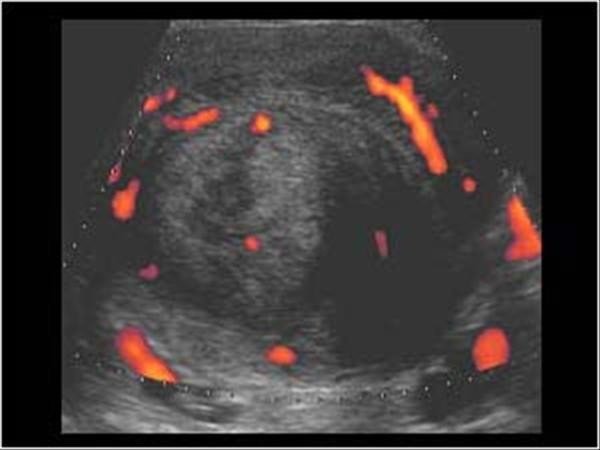

Miyomların genellikle ihmal edildiğine dikkat çeken Kadın Hastalıkları ve Doğum Uzmanı Prof. Dr. Selahattin Kumru, en sık görülen kadın hastalığı olan miyomların tedavisinin kolay olduğunu, tedavi edilmemesi durumunda ise büyük boyutlara ulaşabileceğini ifade etti. Kumru, kanama, kasık ağrısı, kısırlık ve gebelik kaybına neden olabilen, miyom gibi görünen bazı rahim tümörlerinin nadir de olsa kanser hücresi taşıyabileceğini belirtti.

Her 3 kadından 1'inde görülen miyomların en sık rahim tümörü olduğunun altını çizen Kumru, tam olarak neden ortaya çıktığının hala tartışmalı olduğunu ancak genellikle iyi huylu tümörler olduğunu vurguladı. Miyom görünümünde olup içerisinde kötü hücre barındıran (kötü huylu/kanser) olguların oldukça nadir karşılaşıldığını belirten Kumru, yine de takip sırasında hızlı büyüyen miyom görünümlü kitlelerde kanser açısından dikkatli olunması gerektiği konusunda uyardı.

Prof. Dr. Selahattin Kumru, sürekli kasık ağrısı çeken, karında şişlik, adet kanamasının süresinde ya da miktarında artma, ara kanamalar, sık idrara çıkma, kabızlık, cinsel aktivite sırasında ağrı gibi şikayetleri olan kadınların, mutlaka jinekolojik muayene ve ultrasonogafi ile değerlendirilmeleri gerektiğini hatırlattı. Prof. Dr. Kumru, "Halk arasında ultrasonografik olarak miyomu olan olgularda anormal aşırı kanamaların nedeninin genellikle miyomlara bağlandığını, oysa hem miyomların bir kısmının gerçekte miyom görünümlü kanserler olması hem de miyomlar ile birlikte rahim içinde kalınlaşma (endometrial hiperplazi) olması, miyomu olan olguların dikkatli değerlendirilmesini zorunlu kıldığını ifade etti. İhmal edilmiş durumlarda geç kalma ve kanser ise ileri evrelere dönüşme riski mevcuttur" dedi.

Prof. Dr. Kumru şöyle devam etti: "Örneğin rahimin içine doğru büyüyen miyomlar düzensiz kanamalar, gebe kalmakta zorluklar ve düşük (gebelik kaybı) gibi sorunlara neden olurken dışarıya doğru büyüyen miyomlar sessizce kalabilirler ve tesadüfen fark edebilirler. Rahmin ön tarafında bulunan idrar torbasına baskı yapan miyomlar sık sık idrara çıkma ve önde baskı hissine neden olurken arka taraftaki bağırsağa doğru baskı yapan miyomlar dışkılama zorluğu, kabızlık, cinsel ilişki sırasında ağrı gibi şikayetlere neden olabilirler. Yine miyomlar büyüdükçe karında şişlik ve ağrıya neden olabilmektedirler. Bazı hastalar rahim büyüdüğü için karınlarında meydana gelen şişlikleri kilo aldıklarını düşünerek ihmal ederler ve doktora başvurmakta geç kalırlar. Miyomlar nedeniyle aşırı büyümüş rahimler, kalpten çıkan kanın önemli bir kısmı rahime gitmek zorunda olduğu için çabuk yorulma halsizlik, efor kapasitesinde azalma gibi sorunlar da yaşamaktadırlar."

Adet düzensizliği ve kanama fazlalığı yakınması olan bir hastada yine rahim içinden örnekler alındıktan ve kötü bir hastalık olmadığından emin olduktan sonra miyomların çıkarılmasının uygun olacağını belirten Prof. Dr. Kumru, "Sürekli ve uzun süreli kasık ağrılarının (kronik pelvik ağrı) nedeni büyük boyutlara ulaşmış miyomlar ise yine miyom ameliyatı uygun olur. Büyük boyutlara ulaşmış miyomlar rahime giden kan akımı artışına bağlı olarak çabuk yorulma, halsizlik, efor kapasitesinde azalma yapmakta ise yine miyomların ameliyat ile çıkarılması hastanın hayatını daha konforlu hale getirecektir. Tüm bunlara ilave olarak büyük boyutlara ulaşmış ve klasik miyom görünümünden farklı görünümdeki miyomlar da malignite (kanser) riski göz önüne alınarak dikkatli yönetilmelidirler. Sonuç olarak miyomlar, neden olduğu sorunlar, hastaların yaşı, tedaviden beklentileri gibi faktörler göz önüne alınarak yapılan bir değerlendirmeden sonra tedavi edilmeleri önem arz ediyor" diye konuştu.